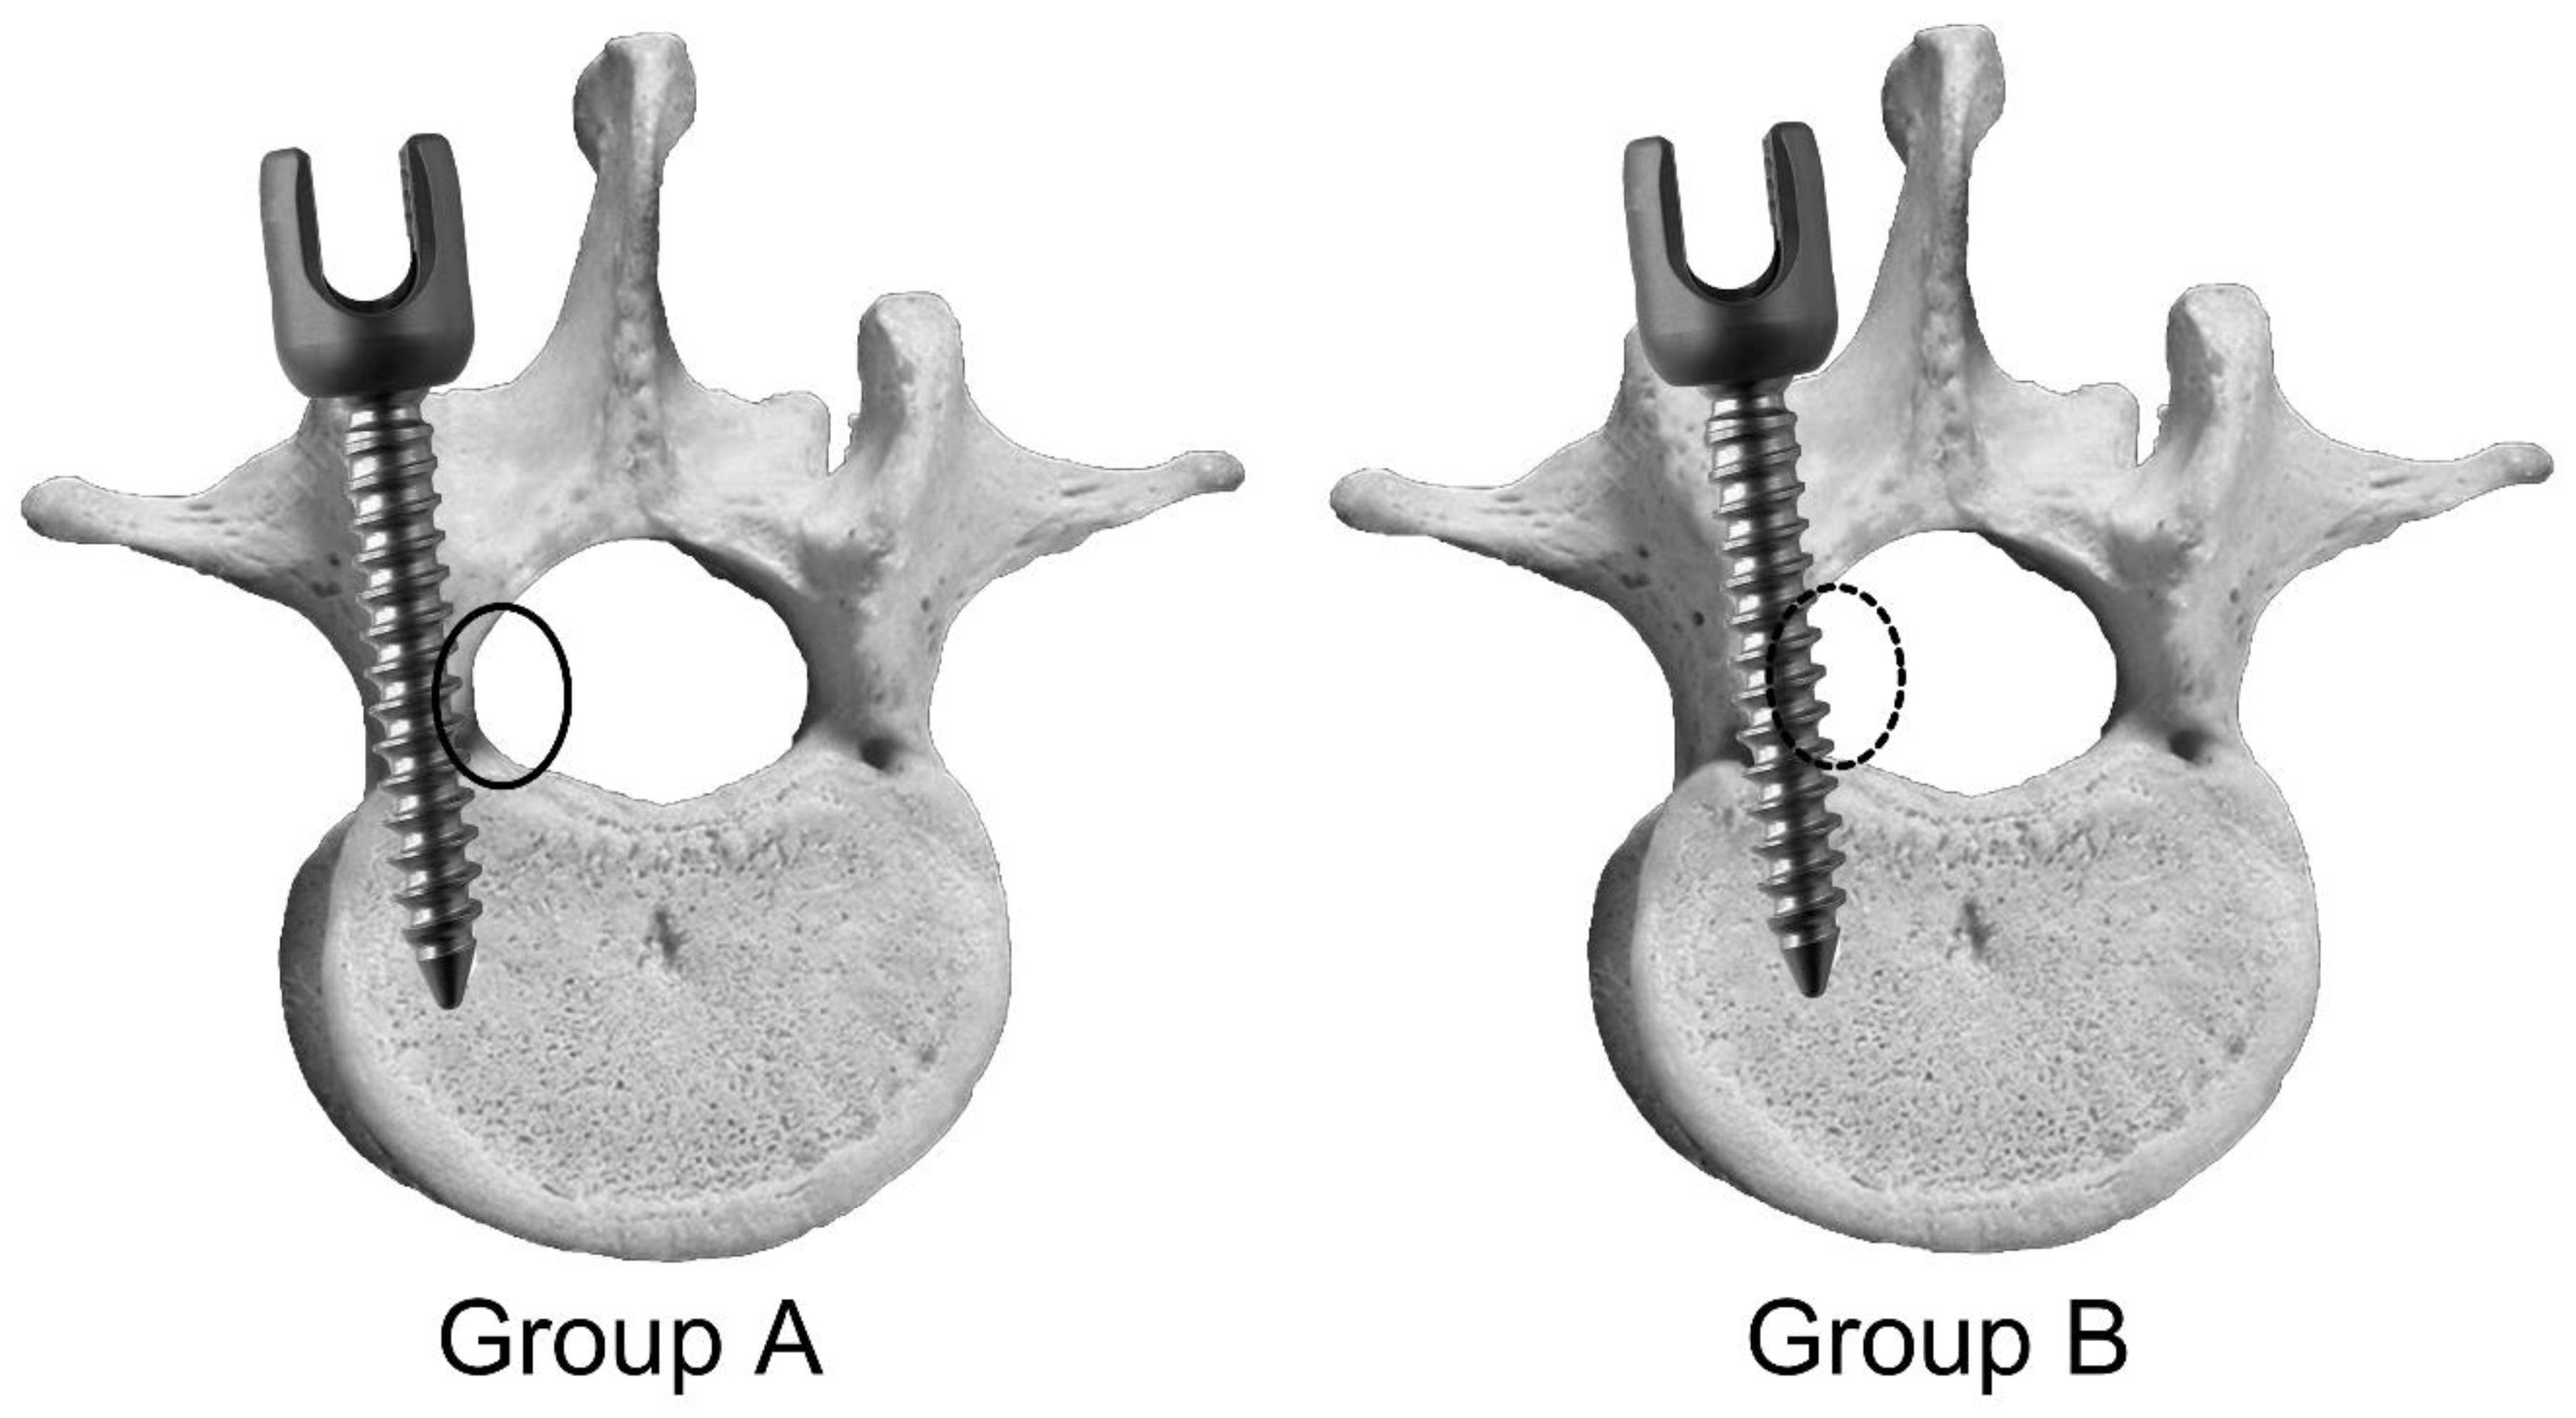

2. Materials and Methods

2.1. Animal Experiment